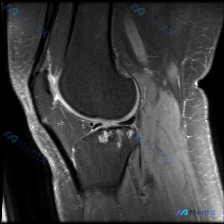

主诉软骨异常,MRI却发现肌腱腱鞘问题?这个诊断陷阱值得警惕

本次仅提供踝关节MRI T1序列轴位图像,核心读片结果如下:

- 骨性结构:胫骨远端、腓骨远端骨质信号正常,骨皮质完整,未见骨折、骨质破坏,关节面轮廓清晰,无明显骨赘形成

- 软组织与肌腱:外踝后方腓骨长短肌腱走行、信号正常;内踝后方胫骨后肌腱、趾长屈肌腱信号正常,但𧿹长屈肌腱(FHL)走行区周围可见局限性圆形液性低信号影,边界清晰,包绕肌腱走行

- 皮下脂肪信号正常,无明显水肿,未见侵袭性软组织肿块

- 关节软骨面本身在T1序列上看轮廓是干净的,没有看到明确的软骨缺损、软骨下骨破坏或者囊性变,没有典型的软骨异常直接证据

- 反而在FHL肌腱腱鞘区,有一个非常明确的边界清晰的囊状低信号病灶,这是目前影像上最确凿的异常发现